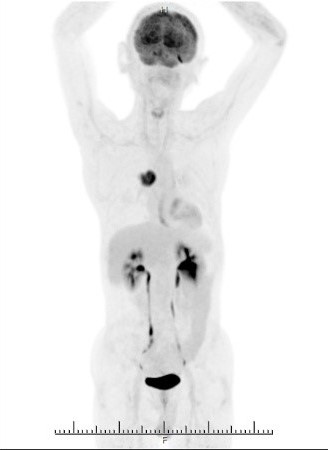

FDG-PET/CT検査画像

肺がん原発巣の症例。(病変部は赤矢印)